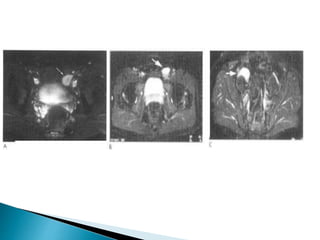

• #17 T1 and T2 weighted axial and coronal sequences, especially with a small field of view (FOV) are advisable as well as diffusion weighted imaging. The testicle is typically low signal on T1 and high signal on T2. The normal testicle exhibits intense diffusion restriction The hyperintensity is consistent with restricted diffusion The normal left testicle is identified lying within the left side of the scrotal sac.  The undescended smaller right testicle is intra-peritoneal in location, lying medial to the right external iliac vessels.

• #18  Transverse STiR images from MRI examinations of patients with undescended testicles (arrow) in the proximal end of the inguinal canal (A) suprapubic pouch (B) and pelvis (C).